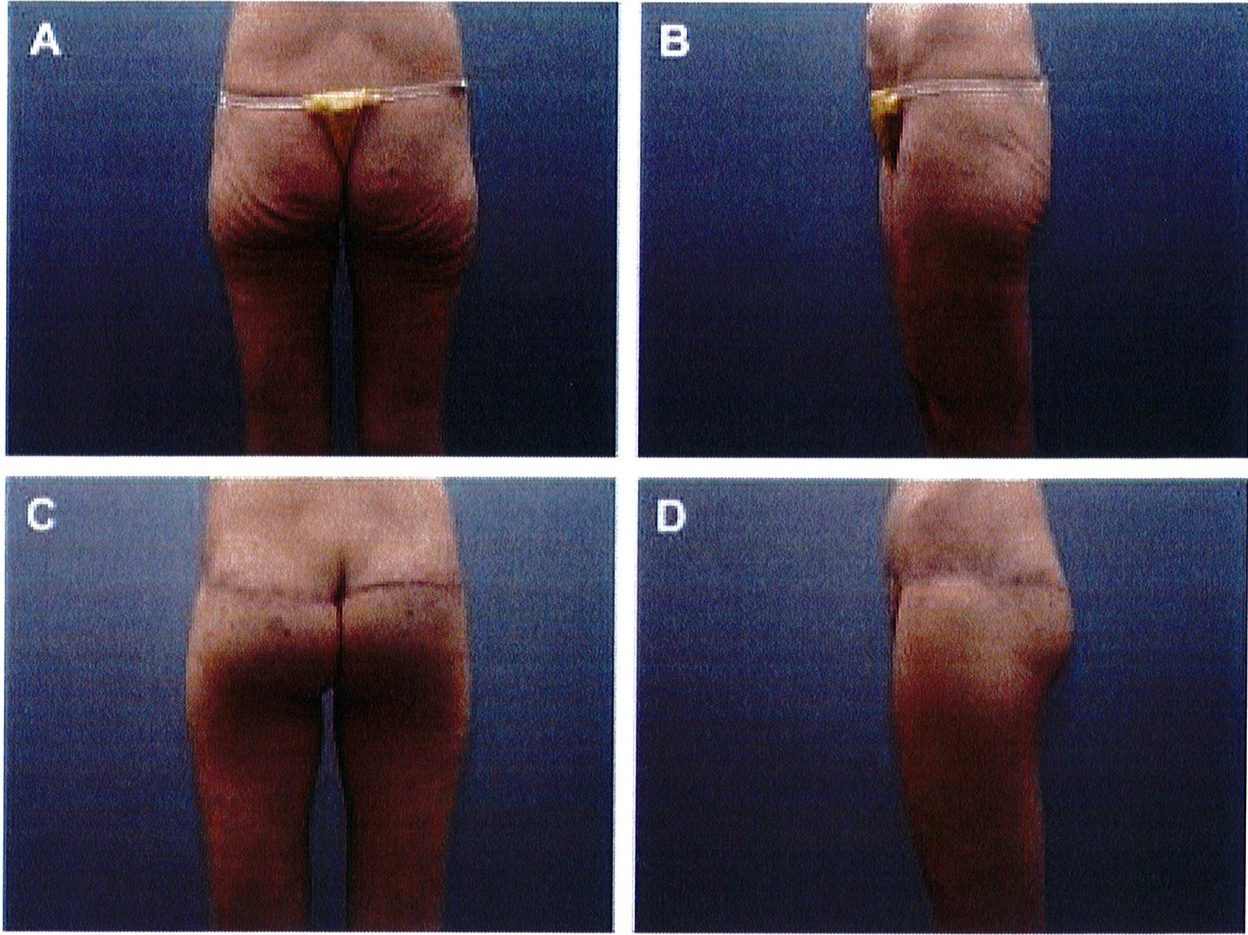

Hình. 11. (A, B) Bệnh nhân nữ 59 tuổi với vùng da mông chùng và xệ. (C,D) Hai năm sau phẫu thuật tạo hình thành bụng và tạo hình mông bằng phương pháp purse-string.Bênh nhân này bị tách vết mổ, sau đó đã đươc điều tri liền seo